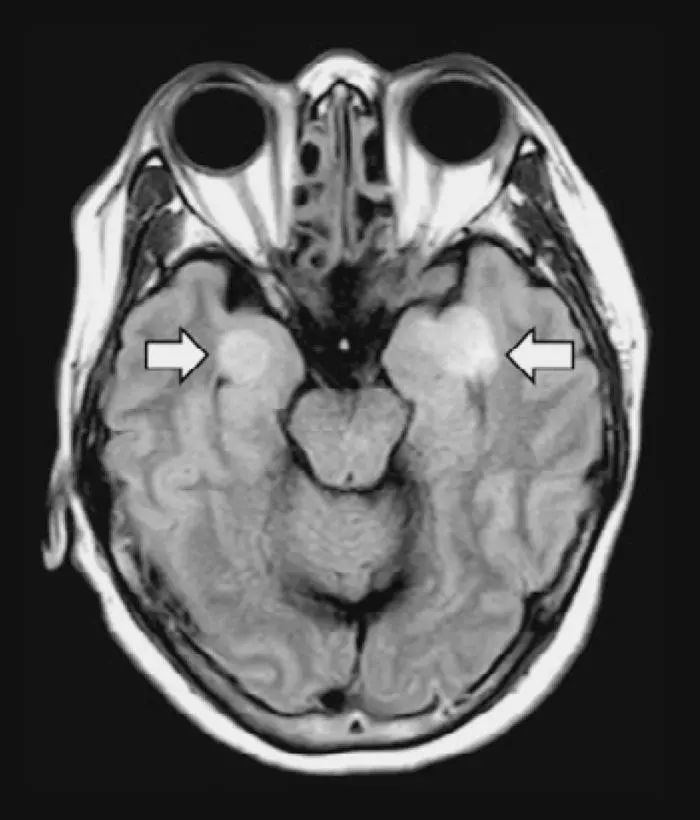

一名患有COVID-19的58岁女性患了脑炎,导致大脑组织受损(箭头)

但是其他因素也可能会损害大脑。例如,细胞因子风暴可能导致脑部肿胀,而血液过度凝结的趋势可能引发中风。现在的问题是,在工作人员专注于挽救生命的时候,从猜想转变为信心,甚至神经系统评估(如诱发呕吐反射或运送患者进行脑部扫描)都有传播病毒的风险。